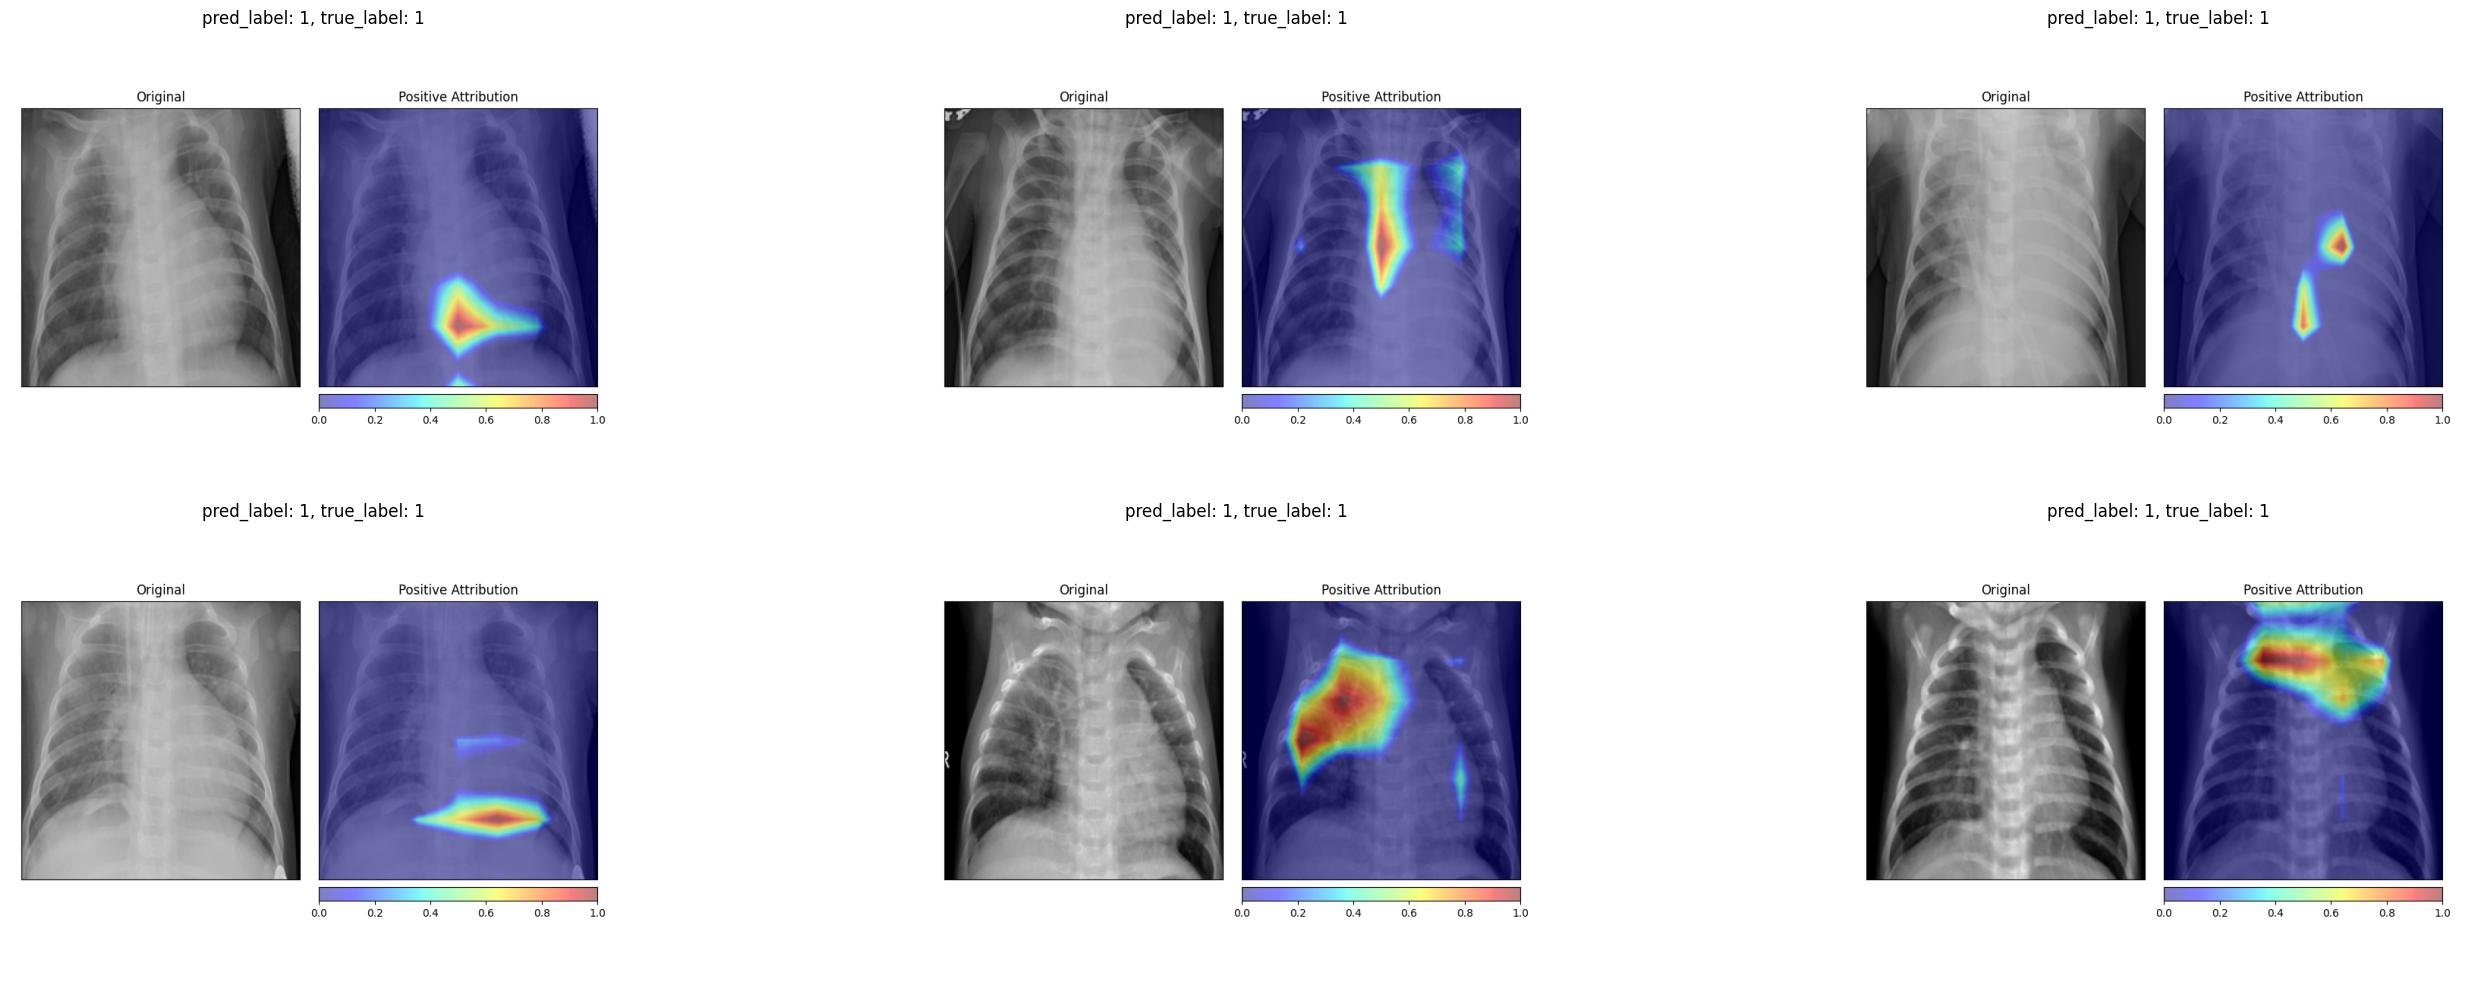

For healthy patients, the Grad-CAM heatmaps concentrate on the central and lower lung regions, highlighting areas where the model confirms normal tissue.

For pneumonia patients, the activation maps expand to cover broader regions of the chest, often focusing on the areas where opacities are visible in the original X-ray. In several examples, the strongest activations align precisely with the haziest regions of the lung fields.

4.3 Comparing the Two Methods

The attribution maps provide reassuring evidence that the model focuses on clinically relevant regions. Grad-CAM in particular highlights areas within the chest cavity that correspond to visible opacities in pneumonia cases. For healthy patients, both methods attribute importance to the lung fields in a way that suggests the model is confirming the absence of pathological findings rather than relying on spurious shortcuts.